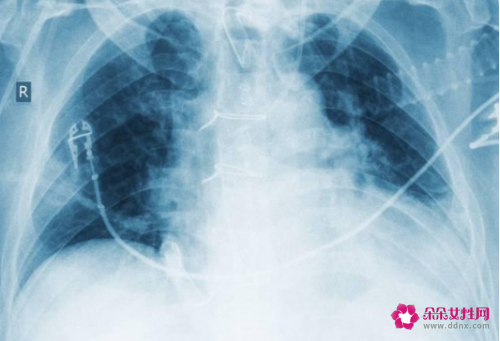

1、肺纤维化

但是就算再好的身体,由于病毒的入侵,康复出院后也避免不了后遗症,出现了肺纤维化,不但会经常呼吸困难,还会全身无力。

而且在有些医院对病人的后继跟踪上也发现,有30%的人员,治愈后都会出现气促,呼吸困难的情况,提示新冠肺炎对肺部的损害非常大。

同时要注意肺纤维化不但会导致呼吸困难,全身无力,影响到人们的生活,发展到后期可能需要进行肺移植。

新型冠状肺炎是否会留下后遗症与新型冠状肺炎的严重程度有关,新型冠状肺炎在临床上分为轻型、普通型、重型和危重型。轻型和普通型的患者一般会完全治愈,不会留下任何后遗症。重型的患者肺部感染很重,有一部分患者会发展成危重型,危重型的患者在临床上并发症相对比较多,肺部可以出现大量的炎性渗出,在临床上称为大白肺,意味着肺炎恢复相对比较慢,可能会引起纤维组织增生,最后形成纤维化,纤维化的患者会有活动后气短等症状。危重型的患者还可以出现其他脏器的并发症,比如肝肾功能损伤,但是一般肝肾功能损伤都是一过性的。目前我国80%的患者都是轻型患者,经过治疗可以完全治愈,只有少部分重型和危重型的患者才会留下后遗症。

1、身体上的,因为新型冠状病毒肺炎主要病位在肺,可能会引起肺部的纤维化改变,以及可能会引起肺功能的损伤。因此新型冠状病毒肺炎患者在日常生活中还需要多做有氧运动,锻炼肺活量,可以多做太极拳、游泳、登山等运动。